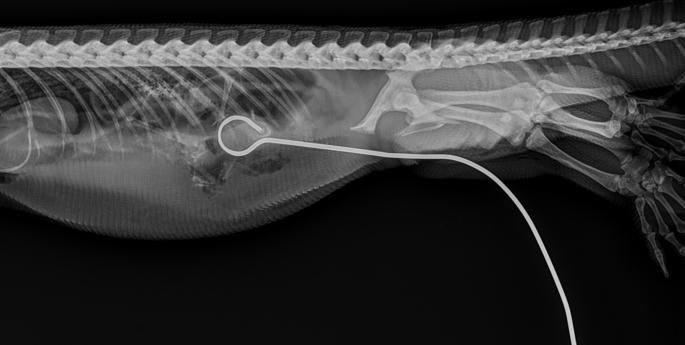

Marine debris has caused terrible injuries to this green sea turtle, now recovering in Wildlife Intensive Care.